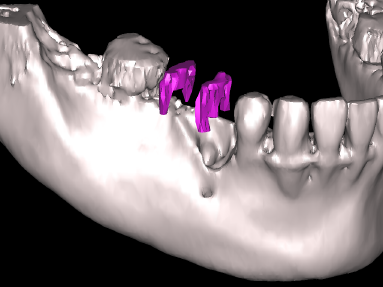

断層撮影

パノラマ撮影だけでなく顎の骨の厚みや形態、根の3次元的な形態を知りたいときは、断層撮影も可能です。これは平面的な像より多くの情報が獲得できます。

CT撮影

インプラントの安全なオペにはCT撮影が必要です。神経や骨などを三次元的に把握することができるからです。当クリニックでは可能なかぎり立体的な分析が必要なケースではCT撮影をするようにしております。(撮影はESTクリニックに依頼)

OP300

歯科用CTと言われている3Dレントゲン撮影機能を搭載したパノーラ19を使用しておりましたがこのほどOP300を新しく導入いたしました.これによりいままで病院に外注していた多数歯の症例も撮影可能になり解像度も飛躍的に向上しました.また3Dの画像も飛躍的に向上したため 患者さんによりわかりやすく説明することができます.